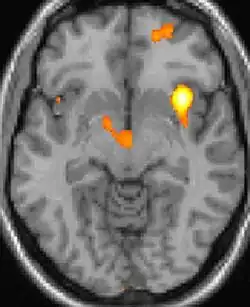

Voxel-based morphometry shows brain area structural differences.

Positron emission tomography (PET) scans indicate the brain areas which are activated during attack only, compared to pain free periods. These pictures show brain areas that are active during pain in yellow/orange color (called "pain matrix"). The area in the center (in all three views) is activated only during cluster headaches. The bottom row voxel-based morphometry shows structural brain differences between individuals with and without CH; only a portion of the hypothalamus is different.[36]